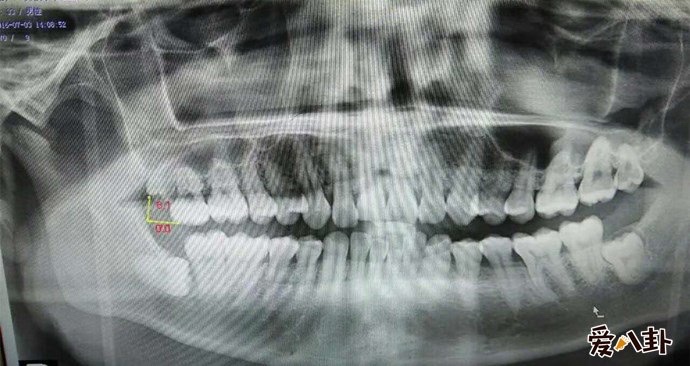

X光下的智齿

说到智齿也就是人们说的智慧齿,智齿实际上是口腔中的第三大臼齿(一般人都有第一和第二大臼齿),因为张智齿的年龄大都是在刚成年的时候,有了智慧所以俗称智慧齿,一般来说有四只智慧齿分别形成始于上下颚骨中,智齿跟其他牙齿一样,但是智齿很不一样的是智齿是最后长出的臼齿,一般智慧齿成形成于9岁而齿冠则于大约14岁形成,并在青春期末长出于口腔中。